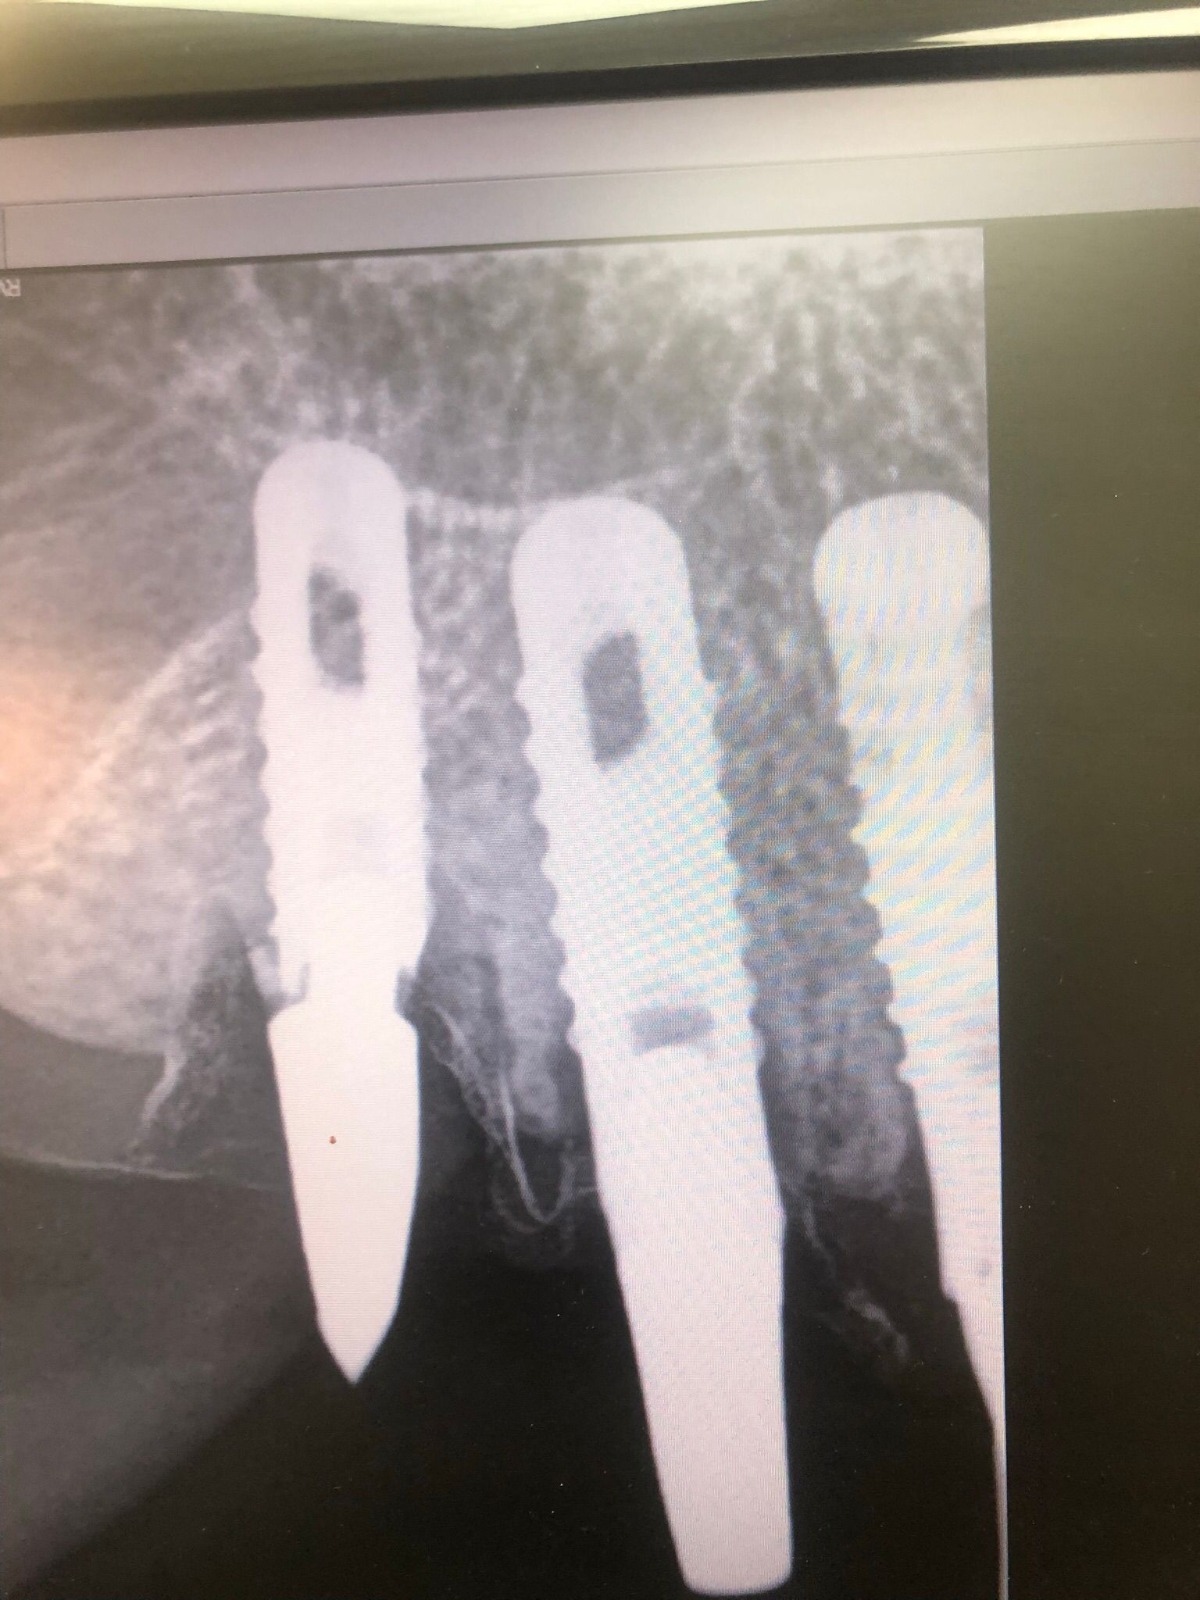

Actualmente vuelve el paciente de nuevo con la misma prótesis. Había roto dos de los tres pilares en concreto los más distales. El primero de los dos había roto la rosca del aditamento dentro del implante como ocurre habitualmente. Pero el ultimo pilar había roto directamente la cabeza del implante tal como se ve en la radiografía y lo que quedaba era un cilindro de titanio macizo perfectamente integrado en el maxilar, sin posibilidad de enroscar nada. Le explicamos al paciente que habría que quitar y poner un implante en el mismo acto. El paciente dijo que no, así que decimos que no se haría cirugía. Buscamos solución alternativa: hacemos un un agujero en el centro del macizo cilíndrico del implante roto y pasamos sucesivamente el set de machos roscantes. Utilizamos una fresa cañón de 1 mm que poco a poco se va introduciendo hasta 8mm con un poco de vagación, que hace que sea un poco mas de 1mm de diámetro. Posteriormente pasamos el conjunto de machos roscantes de métrica 2mm para poder usar un aditamento experimental, que era un palo de rosca de diámetro 2 mm unido a un cuerpo metálico en forma de sombrero napoleónico fabricado en cromo/cobalto, prototipos primitivos de la sistemática ASATIM y que tienen la característica de tener gran resistencia a la fractura. Nos llevó un tiempo largo el tallado de dichos aditamentos, tal como se puede observar en las imágenes, y tras cicatrizar la encía se le hizo una prótesis estándar. Esperemos que no lo rompa más veces.